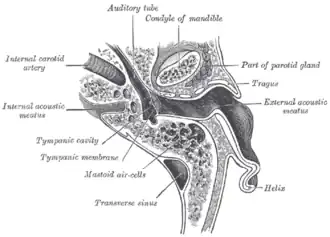

Middle ear, with auditory tube at bottom right | |

The Eustachian tube extends from the anterior wall of the middle ear to the lateral wall of the nasopharynx, approximately at the level of the inferior nasal concha. It consists of a bony part and a cartilaginous part.

The bony part (1⁄3) nearest to the middle ear is made of bone and is about 12 mm in length. It begins in the anterior wall of the tympanic cavity, below the septum canalis musculotubarius, and, gradually narrowing, ends at the angle of junction of the squamous and the petrous parts of the temporal bone, its extremity presenting a jagged margin which serves for the attachment of the cartilaginous part.[5] The vestibule of the Eustachian tube is known as the protympanum,[6] The protympanum is also known as the anterior part of the bony part of the tube.[7]

The cartilaginous part of the Eustachian tube is about 24 mm in length and is formed of a triangular plate of elastic fibrocartilage, the apex of which is attached to the margin of the medial end of the bony part of the tube, while its base lies directly under the mucous membrane of the nasal part of the pharynx, where it forms an elevation, the torus tubarius or cushion, behind the pharyngeal opening of the auditory tube.

The upper edge of the cartilage is curled upon itself, being bent laterally so as to present on transverse section the appearance of a hook; a groove or furrow is thus produced, which is open below and laterally, and this part of the canal is completed by fibrous membrane. The cartilage lies in a groove between the petrous part of the temporal bone and the great wing of the sphenoid; this groove ends opposite the middle of the medial pterygoid plate. The cartilaginous and bony portions of the tube are not in the same plane, the former inclining downward a little more than the latter. The diameter of the tube is not uniform throughout, being greatest at the pharyngeal opening, least at the junction of the bony and cartilaginous portions, and again increased toward the tympanic cavity; the narrowest part of the tube is termed the isthmus.

The Eustachian tube is derived from the dorsal part of the first pharyngeal pouch and second endodermal pouch, which during embryogenesis forms the tubotympanic recess. The distal part of the tubotympanic sulcus gives rise to the tympanic cavity, while the proximal tubular structure becomes the Eustachian tube. It helps transformation of sound waves.